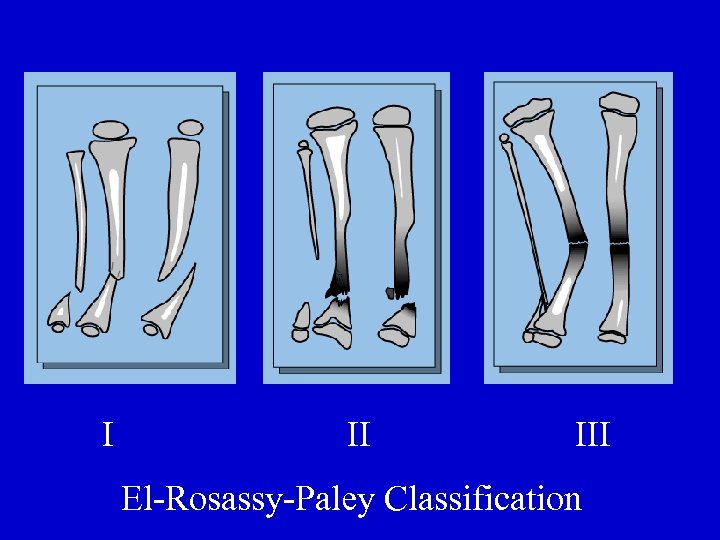

I II III El-Rosassy-Paley Classification

Type I • Atrophic, narrow bone ends • Mobile • No previous surgery El-Rosassy-Paley Classification

Type II • Atrophic, narrow bone ends • Mobile • Previous surgery El-Rosassy-Paley Classification

Type III • Hypertrophic, wide bone ends • Stiff • Previous surgery El-Rosassy-Paley Classification